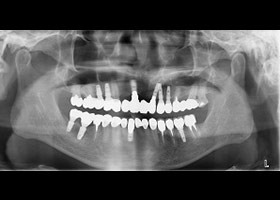

病患:55歲 男性

主訴:多顆缺牙,想全口治療。

多顆缺牙、牙周病、多顆蛀牙。

治療前

多顆缺牙及牙周病、蛀牙